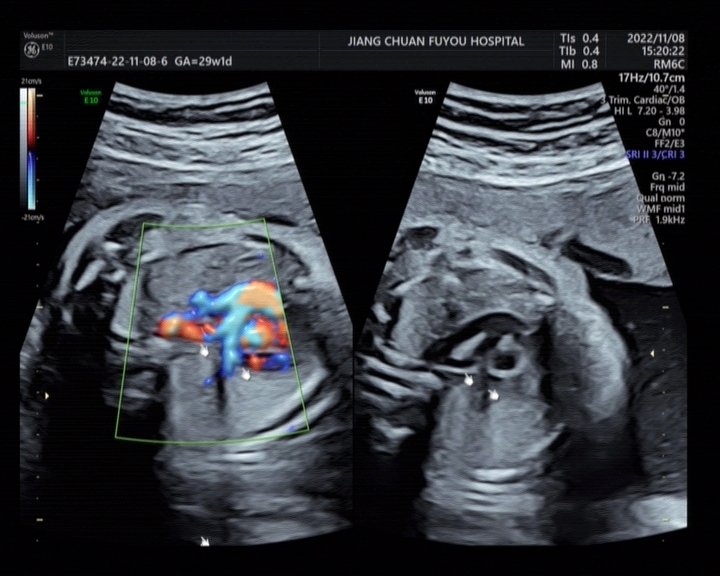

近日,孕妈刘XX到江川区妇幼保健院影像科行胎儿彩超检查时,经过江川区妇幼保健院超声医师耐心细致检查后,诊断为罕见病—“胎儿肺动脉吊带并永存左上腔”。 该孕妇 24岁,身体健康, 否认遗传病史。到江川区妇幼保健院影像科行胎儿超声检查,发现胎儿左肺动脉起源于正常的右肺动脉,并从气管右侧及后方走行进入左肺合并三血管气管切面,肺动脉左侧探及一血管横切面。超声提示如下图:

随即建议到上级医院行胎儿超声心动图检查。经后期随访,该孕妇到上级医院检查后,其结果与江川区妇幼保健院诊断一致。 永存左上腔和肺动脉吊带属于先天性心血管畸形。永存左上腔,大部分胎儿出生后无临床症状,不需要治疗;肺动脉吊带(PAS) 又名“迷走左肺动脉”,属于血管环的一种。 血管环的发病率占所有先天性心脏病的 0.8%~1.3%, 而肺动脉吊带约仅占血管环畸形的 3%~ 6%,十分罕见。肺动脉吊带患者首次出现症状多为1天至4个月,90%可再生后不久即可出现明显呼吸道症状,最常表现为气促、喘鸣及咳嗽,喂奶困难和发育延缓,严重者还有呼吸困难、发绀、窒息和呼吸暂停等,可引起意识丧失、抽搐甚至死亡。呼吸道感染或喂奶引起的反流吸入可使病情恶化,如无有效治疗病死率可达 90%。